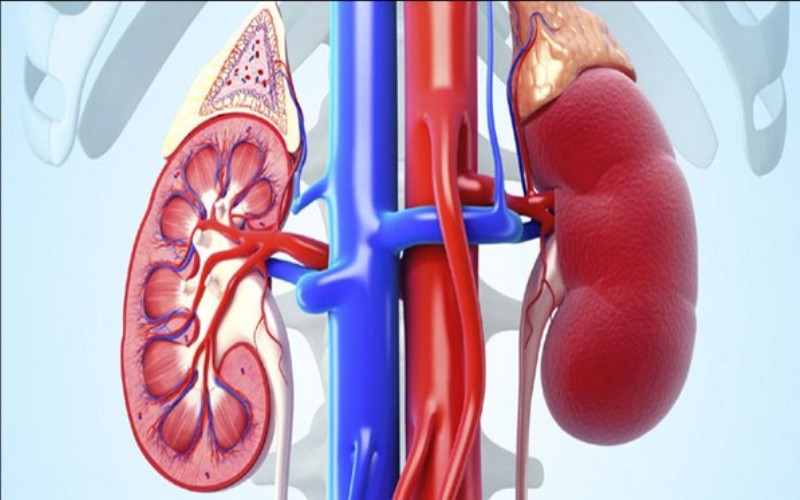

Washington: A new study saw scientists identify an enzyme that, if suppressed, can trigger renal failure.

The study, published in Nature Communications, saw a global research team, led by the University of Bristol study how the activity of the enzyme GSK3 (Glycogen Synthase Kinase 3) affects the function of podocyte cells, which are crucial in enabling the kidneys to filter blood.

In the podocyte, the GSK3 (which are of two types) enzyme stops the body from leaking protein into the urine and so prevents the development of kidney failure. However, when both GSK3 forms are excessively suppressed, they become highly detrimental both in a developing kidney and in a fully mature kidney, increasing the likelihood of renal failure.